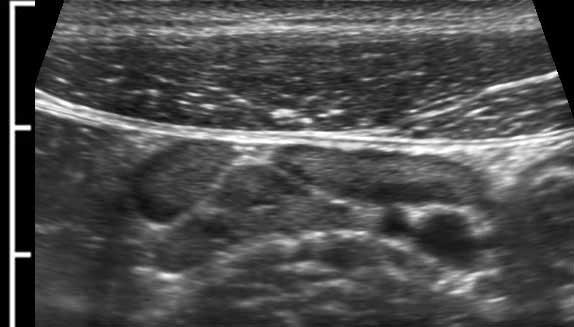

Lưu ý tình trạng tăng sản lymphoid của các mảng Peyer ở hồi tràng đoạn cuối.

Đây là hình ảnh của hồi tràng tận cùng ở ba trẻ em và người trẻ tuổi khác nhau với các mảng Peyer lớn biểu hiện dưới dạng dày lớp niêm mạc sâu không đối xứng, giảm âm.

Với mỗi kháng nguyên mới, mô bạch huyết lại được tái hoạt hóa.

Ở bệnh nhân trẻ tuổi, cả hạch bạch huyết mạc treo ruột và các mảng Peyer đều lớn hơn nhiều so với người trưởng thành – kể cả về kích thước tuyệt đối.

Mô bạch huyết bị kích thích ở trẻ em không chỉ dẫn đến các mảng Peyer nổi bật ở hồi tràng đoạn cuối và các hạch bạch huyết mạc treo ruột phì đại (hình dưới bên trái), mà còn gây ra tình trạng dày lớp niêm mạc sâu của ruột thừa (hình dưới bên phải).

Lưu ý rằng các phần lồi ra –đôi khi giống polyp- (góc trên bên phải), có thể đóng vai trò là điểm dẫn đầu trong lồng ruột hồi-manh tràng điển hình ở trẻ nhỏ

Mặc dù mô bạch huyết ở hồi tràng tận cùng thể hiện rõ nét nhất ở trẻ nhỏ, nhưng nó vẫn có thể được tìm thấy cho đến năm 20 tuổi.

Ở người thanh niên 15 tuổi này bị viêm ruột thừa cấp tính (đầu mũi tên), vẫn còn các mảng Peyer (p.) nổi bật ở lớp niêm mạc sâu của hồi tràng đoạn cuối.

Ở trẻ em, lớp niêm mạc sâu có thể cho thấy sự dày lên giảm âm đáng kể do tăng sản mô bạch huyết, điều này cũng có thể khiến ruột thừa kém bị nén hơn.

Đây là một phát hiện thường gặp ở trẻ em khỏe mạnh, nhưng trong trường hợp tăng sản rất rõ rệt, có thể có sự hiện diện của nhiễm virus.

Note the complete absence of inflamed fat.